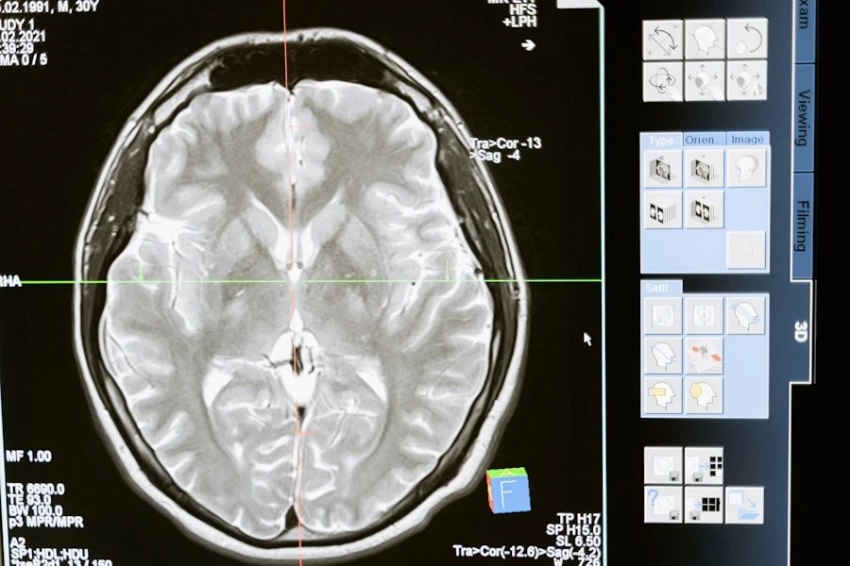

Фото из открытых источников Ученым из университета Хериот-Уотт, что в британском Эдинбурге, удалось осуществить новое успешное ультразвуковое исследование, способное обнаруживать рак простаты всего за 20 минут. Как пишет Daily Mail, инновационный подход значительно сокращает время диагностики в сравнении...